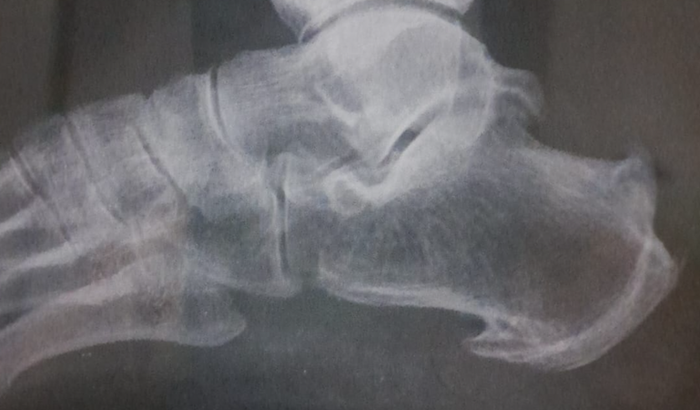

OLÁ MEU NOME É RISALVA MARIA MORO EM JOÃO PESSOA/PB TENHO 57 ANOS ,E SOFRO A BASTANTE TEMPO COM ESSE MEU PÉ JÁ FOI FEITO TODOS OS TRATAMENTOS POSSÍVEIS COMO FISIOTERAPIA,ANTI-INFLAMATÓRIO ,ATÉ SAPATO ORTOPÉDICO, USO DE INJEÇÃO NO OSSO E TUDO Q FOI RECOMENDADO PELOS MÉDICOS. E CADA DIA MAIS VAI FICANDO PIOR AS DORES SÓ AUMENTAR TEM DIA QUE NÃO CONSIGO NEM COLOCAR O PÉ NO CHÃO,FUI SEGUNDA-FEIRA AO MEDICO ORTOPEDISTA DIA 19/06/20023 , ELE FALOU QUE MEU PÉ TEM QUE FAZER UMA CIRURGIA POIS O OSSO ESTA MUITO GRANDE,ESSES TRATAMENTO NÃO VAI MAIS ADIANTA,EU PRECISO MUITO FAZER ESSA CIRURGIA DOE MUITO,QUEIMA E MESMO COM PÉ ASSIM TENHO QUE IR TRABALHAR POIS PRECISO,SO NÃO TENHO CONDIÇÕES DE PAGAR ,PEGO DOIS ÔNIBUS ,TRABALHO PÉ O MEDICO DISSE:COMO VOCÊ ESTÁ AGUENTANDO.